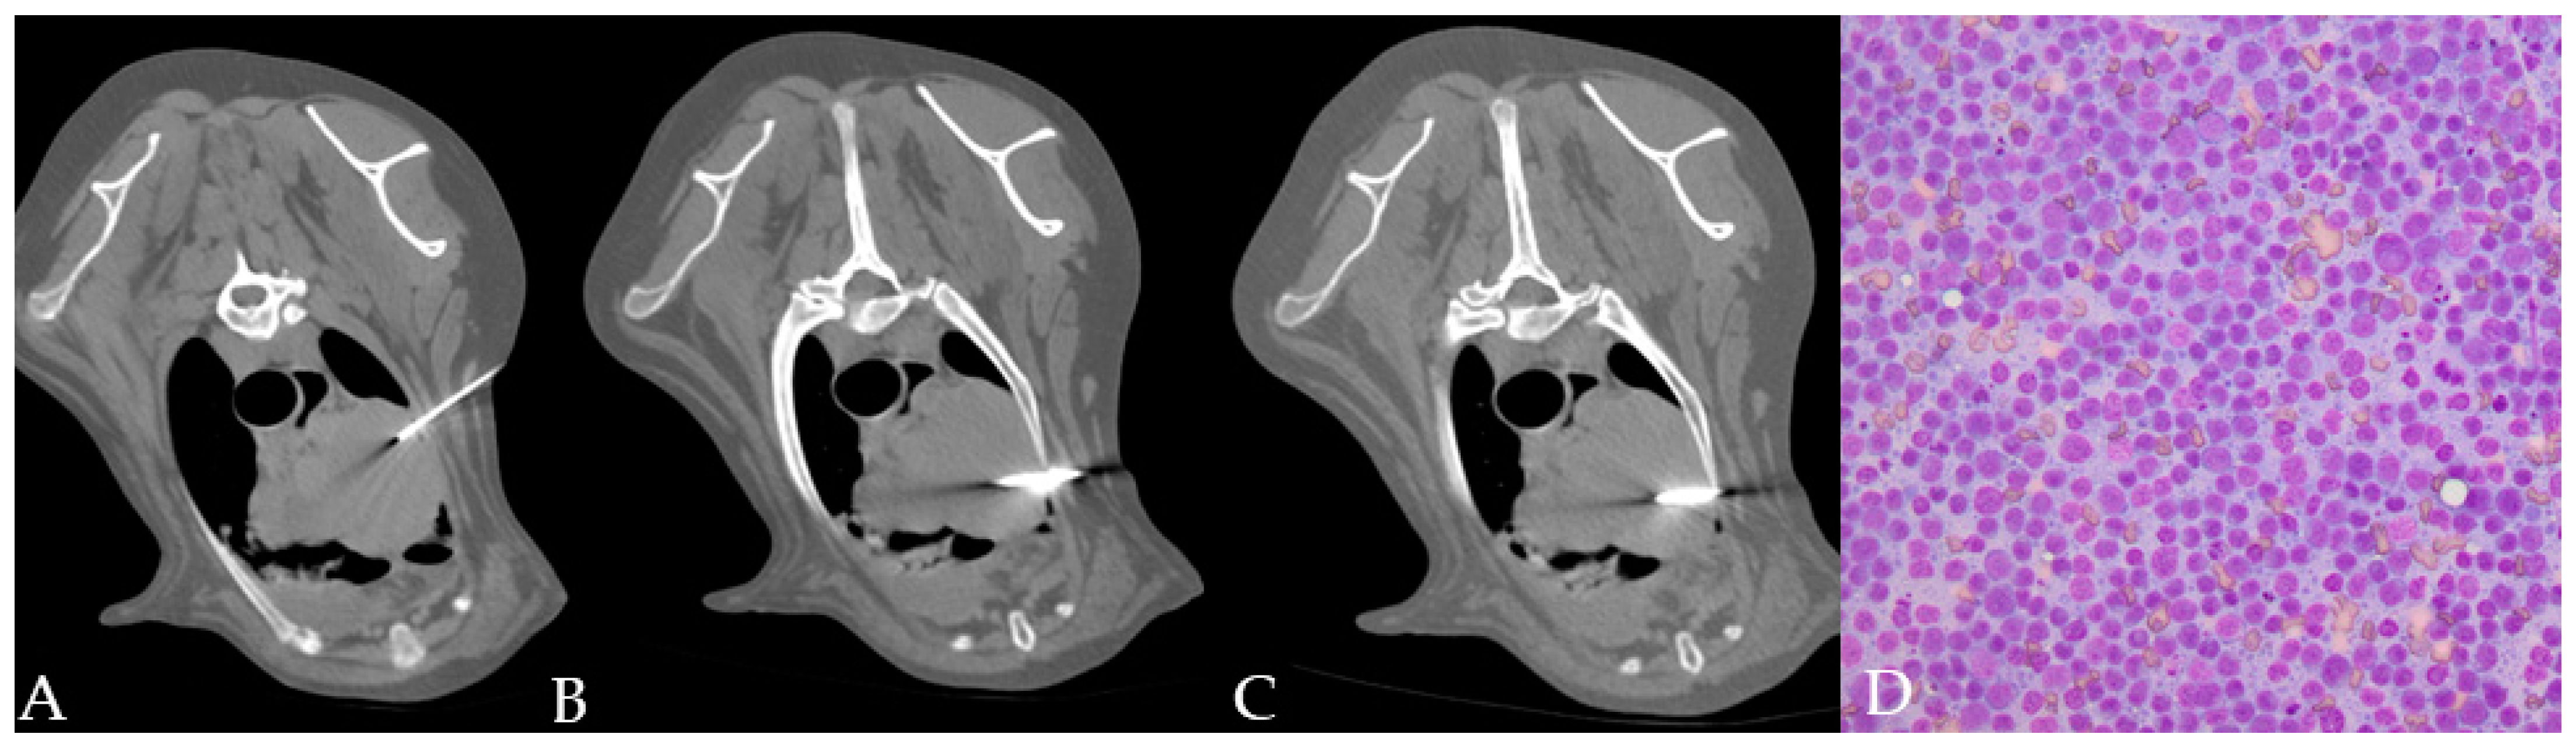

From www.researchgate.net

Representative photomicrographs of the dog’s liver biopsy sample. (A How Much Does A Liver Biopsy Cost For A Dog We offer exceptional value, service and care. A basic blood test can cost between £50 and £100, while more advanced tests like ct scans or biopsies can cost up to £1,000. 47 rows at msm vets we offer a transparent pricing policy for surgical procedures and mentoring. A liver biopsy in dogs is usually never the first step when the. How Much Does A Liver Biopsy Cost For A Dog.